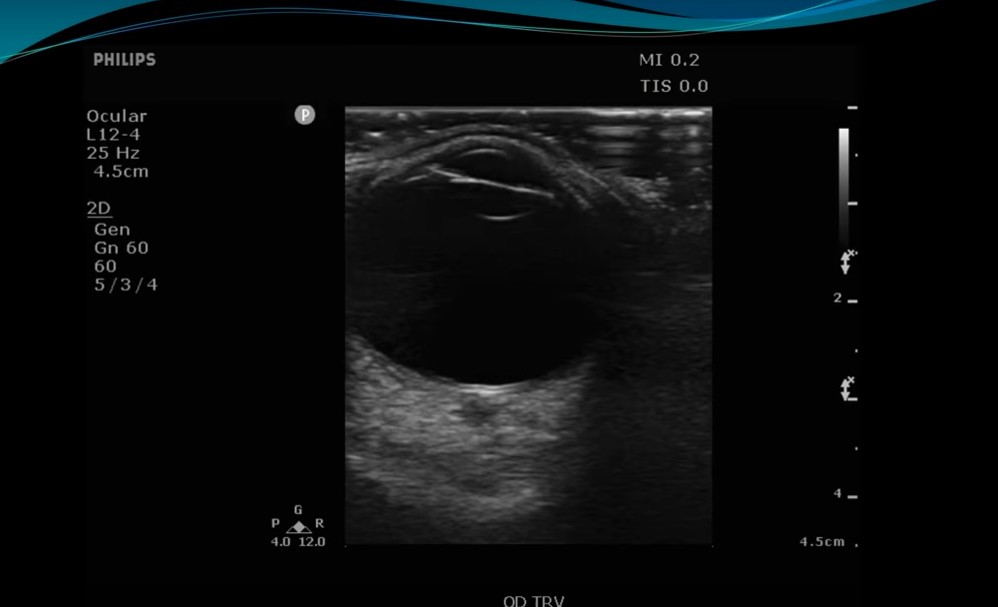

Apr 25, 2025 Guardians of the Sound2:263:554:025:29 Very important to anchor your arm on the shoulder [see right picture] to avoid putting any pressure on the globe]. Review transcript on YouTube 5:39 – 6:166:277:16 In both views the patient is asked to look right and left and up and down.7:367:56 You need an ophthalmology setting on your machine so that you don’t exceed the safe TI and MI.8:018:328:459:029:119:5710:2910:3610:4010:4511:1211:3511:5012:4013:05 Warning Use only eye settings. Don’t use the MSK setting in the picture below: